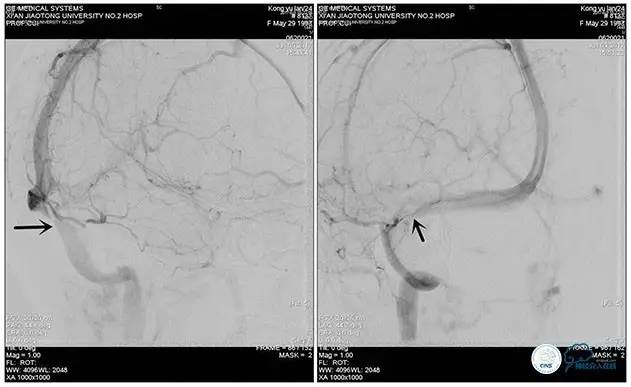

右侧ICA造影正侧位

右侧ICA造影斜位

右侧ICA正侧位

右侧ICA斜位

静脉淤滞

左侧ICA斜位

左侧VA正斜位

术中测压

远端压力:530mmH2O

近端压力:120mmH2O

术中造影

术后造影

狭窄较前有改善